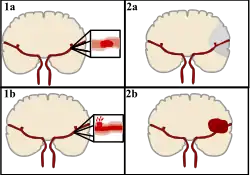

There are two main categories of stroke. Ischemic (top), typically caused by a blood clot in an artery (1a) resulting in brain death to the affected area (2a). Hemorrhagic (bottom), caused by blood leaking into or around the brain from a ruptured blood vessel (1b) allowing blood to pool in the affected area (2b) thus increasing the pressure on the brain.

Stroke can be classified into two major categories: ischemic and hemorrhagic.[20] Ischemic stroke is caused by interruption of the blood supply to the brain, while hemorrhagic stroke results from the rupture of a blood vessel or an abnormal vascular structure.

About 87% of stroke is ischemic, with the rest being hemorrhagic. Bleeding can develop inside areas of ischemia, a condition known as "hemorrhagic transformation." It is unknown how many cases of hemorrhagic stroke actually start as ischemic stroke.[2]